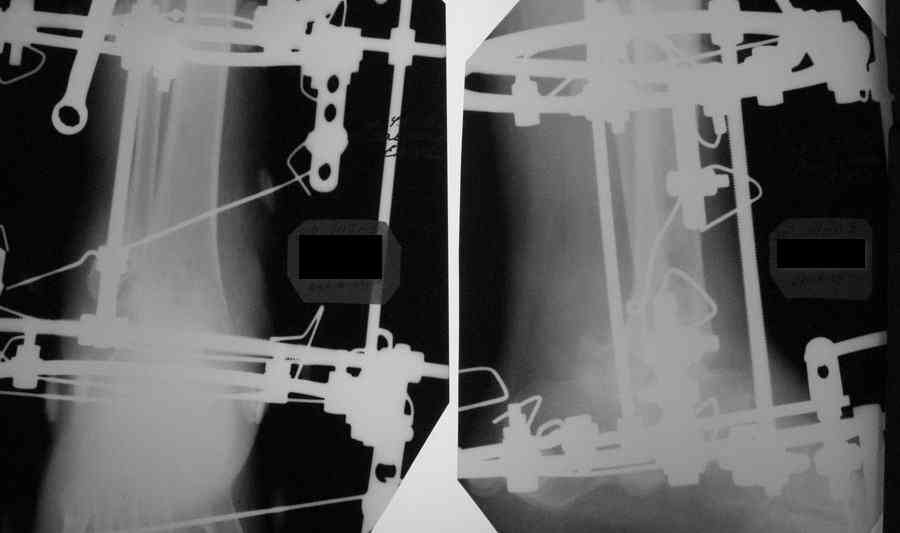

Re: Артродез г/стопного сустава

Александр Николаевич! Постарался переделать рентгенограмму - не знаю лучше ли стало- снимки никудышные:(

Что касается подтаранного сустава, то постарался его максимально разгрузить.